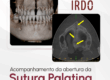

Nesta análise tridimensional de perda óssea, a tomografia a evidencia significativamente ao redor do implante, permitindo uma avaliação detalhada da progressão da reabsorção e seu impacto estrutural.

O que os cortes tomográficos revelam?

Comprometimento ósseo peri-implantar – A imagem mostra uma área de reabsorção óssea ao redor do implante, indicando um possível processo inflamatório ou falha na osseointegração. Em síntese, a extensão da perda pode impactar a estabilidade do implante e a longevidade da reabilitação.

Atingimento da cortical óssea – A análise tridimensional de perda óssea em diferentes planos permite observar o envolvimento da cortical vestibular e lingual, que pode estar afinada ou rompida. Isso, um fator determinante para a conduta clínica e necessidade de regeneração óssea.

Proximidade com estruturas anatômicas – É possível visualizar a relação do implante com estruturas críticas, como o canal mandibular.